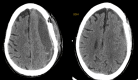

Background Chronic subdural hematoma (CSDH) is a common neurosurgical problem, which offers a good outcome following surgery. In many cases, burr hole irrigation and drainage under local anesthesia can provide satisfactory results. However, recurrence can be a cause for concern for both the surgeon and the patient. While recurrence is not a frequent phenomenon, studies have reported rates of up to 31.6%. Aims and objectives In this study, our objective is to examine a comprehensive range of potential risk factors and provide valuable insights into identifying patients at a higher risk of recurrence to aid in surgical decision-making. Methodology This study employed a prospective and retrospective design, conducted between 2017 and 2021, at Sri Ramachandra Institute of Higher Education and Research. The study received ethical approval from the Institutional Ethics Committee. The research aimed to assess patients who underwent surgery for CSDH, with a particular focus on those who experienced recurrence. Results The average age of patients with recurrence was 71.5 years compared to 65.2 years in the no-recurrence group, but this difference did not show a significant statistical correlation. A significant male predominance was observed, with 27 men and four women affected (out of a total of 147 men and 73 women in the study), resulting in a statistically significant p-value of 0.01. On multivariate analysis, heterogenous subtypes were a significant predictor of recurrence (OR: 8.88, 95% CI: 6.96-16.54, p = 0.01). The mean midline shift in those with recurrence was 11.4 mm compared to 7.09 mm in those without recurrence. This was a statistically significant correlation with a p-value of 0.02. Regarding those with recurrence, 24 patients underwent evacuation using two burr holes, with one placed in the frontal region and another in the parietal region. All of these patients had a subdural drain placed, which was removed on postoperative day 2. The remaining eight patients underwent a mini-craniotomy for evacuation. We had four cases of refractory CSDH, all of whom underwent the second evacuation using burr holes. Three of them underwent evacuation via craniotomy, while the family of the fourth patient did not give consent for the procedure. Conclusion Patient-related factors such as gender, bilateral presentation, and the presence of hypertension and radiological factors such as the presence of heterogenous subtype and a significant midline shift are clues toward a higher chance of recurrence.